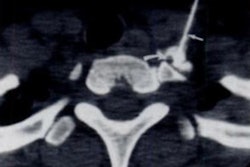

To do this, they performed a study that included 534 patients (with 565 chronic total occlusion lesions) from a single hospital that made up the deep-learning algorithm training set and 186 patients (with 189 CTOs) from three different hospitals that made up the test set. All study participants underwent a CCTA exam a month before having a percutaneous coronary intervention; study endpoints were guidewire crossing within 30 minutes and PCI success.